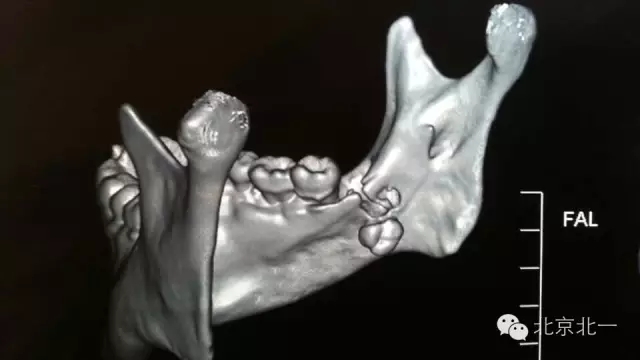

圖二:CBCT掃描重建清晰看到舌側(cè)骨板骨折,牙根位于舌側(cè)。而不是進入下牙槽神經(jīng)管。

640.webp (1).jpg